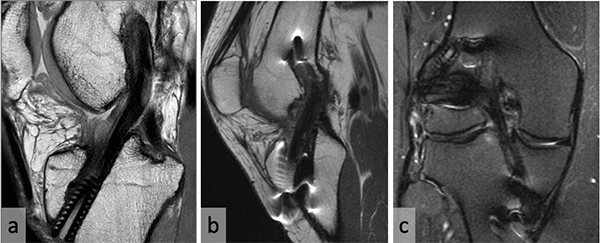

En la evaluación radiográfica de ambos grupos no se observaron cambios degenerativos. En la RM, al cumplir un año de la cirugía, 66% del Grupo 1 (Fig. 3a), y 61% del Grupo 2 (Figs. 3b y 3c) presentaban una intensidad homogénea (grado 1) del neoligamento.

Figura 3. a) Resonancia magnética al año postoperatorio de revisión de LCA. b y c) RM de revisión de LCA más plástica extraarticular lateral. Nótese el neoligamento homogéneo y continuo en ambos pacientes.